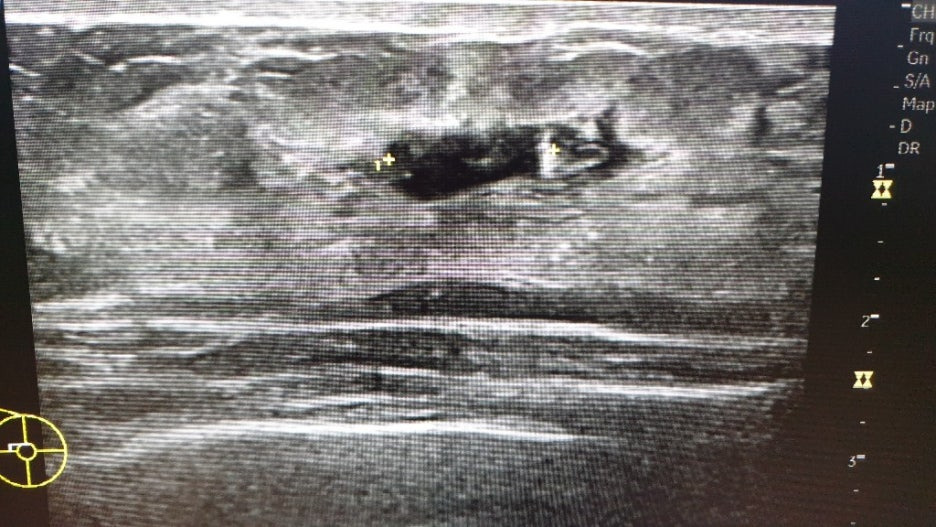

힐끗힐끗 화면을 보니 작고 둥근 것들이 보였고, 여러 번 길이를 재는 것이 보였어요. 엑스레이 상으로는 깨끗했던 오른쪽 가슴에도 혹이 보였어요. (점점 불안해지기 사작했습니다...)

왼쪽 2.3cm / 오른쪽 1.4cm + 기타 작은 혹 몇 개

크기보다 모양이 더 중요하다고 하더군요. 일단 동글동글하면 괜찮은 것이고 뾰족뽀족하게 생기면 악성일 가능성이 크다고 합니다.

모양이 나쁘지는 않지만 크기가 1cm 이상이면 작은 것은 아니므로 조직 검사를 하자고 하더군요. 조직 검사를 해서 이 혹이 어떤 혹인지 정확하게 확인 후 치료 방법 등을 생각해 보자고 하셨어요.